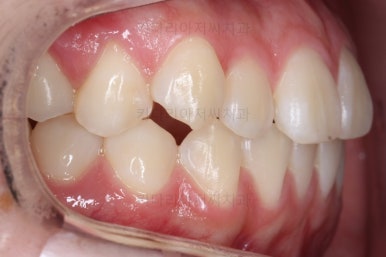

각각 왼쪽, 오른쪽의 교합의 모습입니다.

가장 좋은 교합은 위아래 치아들이 지그재그로 톱니바퀴 물리듯이 맞아들어가야 하는데 오른쪽 사진들 보면 중간중간 빈틈도 많이 보여요.

이런 교합은 장기적으로 치아 수명을 단축시킬 수 있습니다.

왼쪽이 치료 초기의 교합 모습, 오른쪽이 치료 마무리 시점의 교합입니다.

빈틈이 많았던 교합이 많이 개선된 것이 보이시죠?

이러한 이유 때문에 전체교정이 필요했답니다.